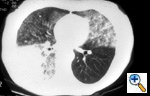

Fig.

1b: Computed tomographic

scan of the chest (lung

windows) shows the above

findings to greater advantage, TX. |